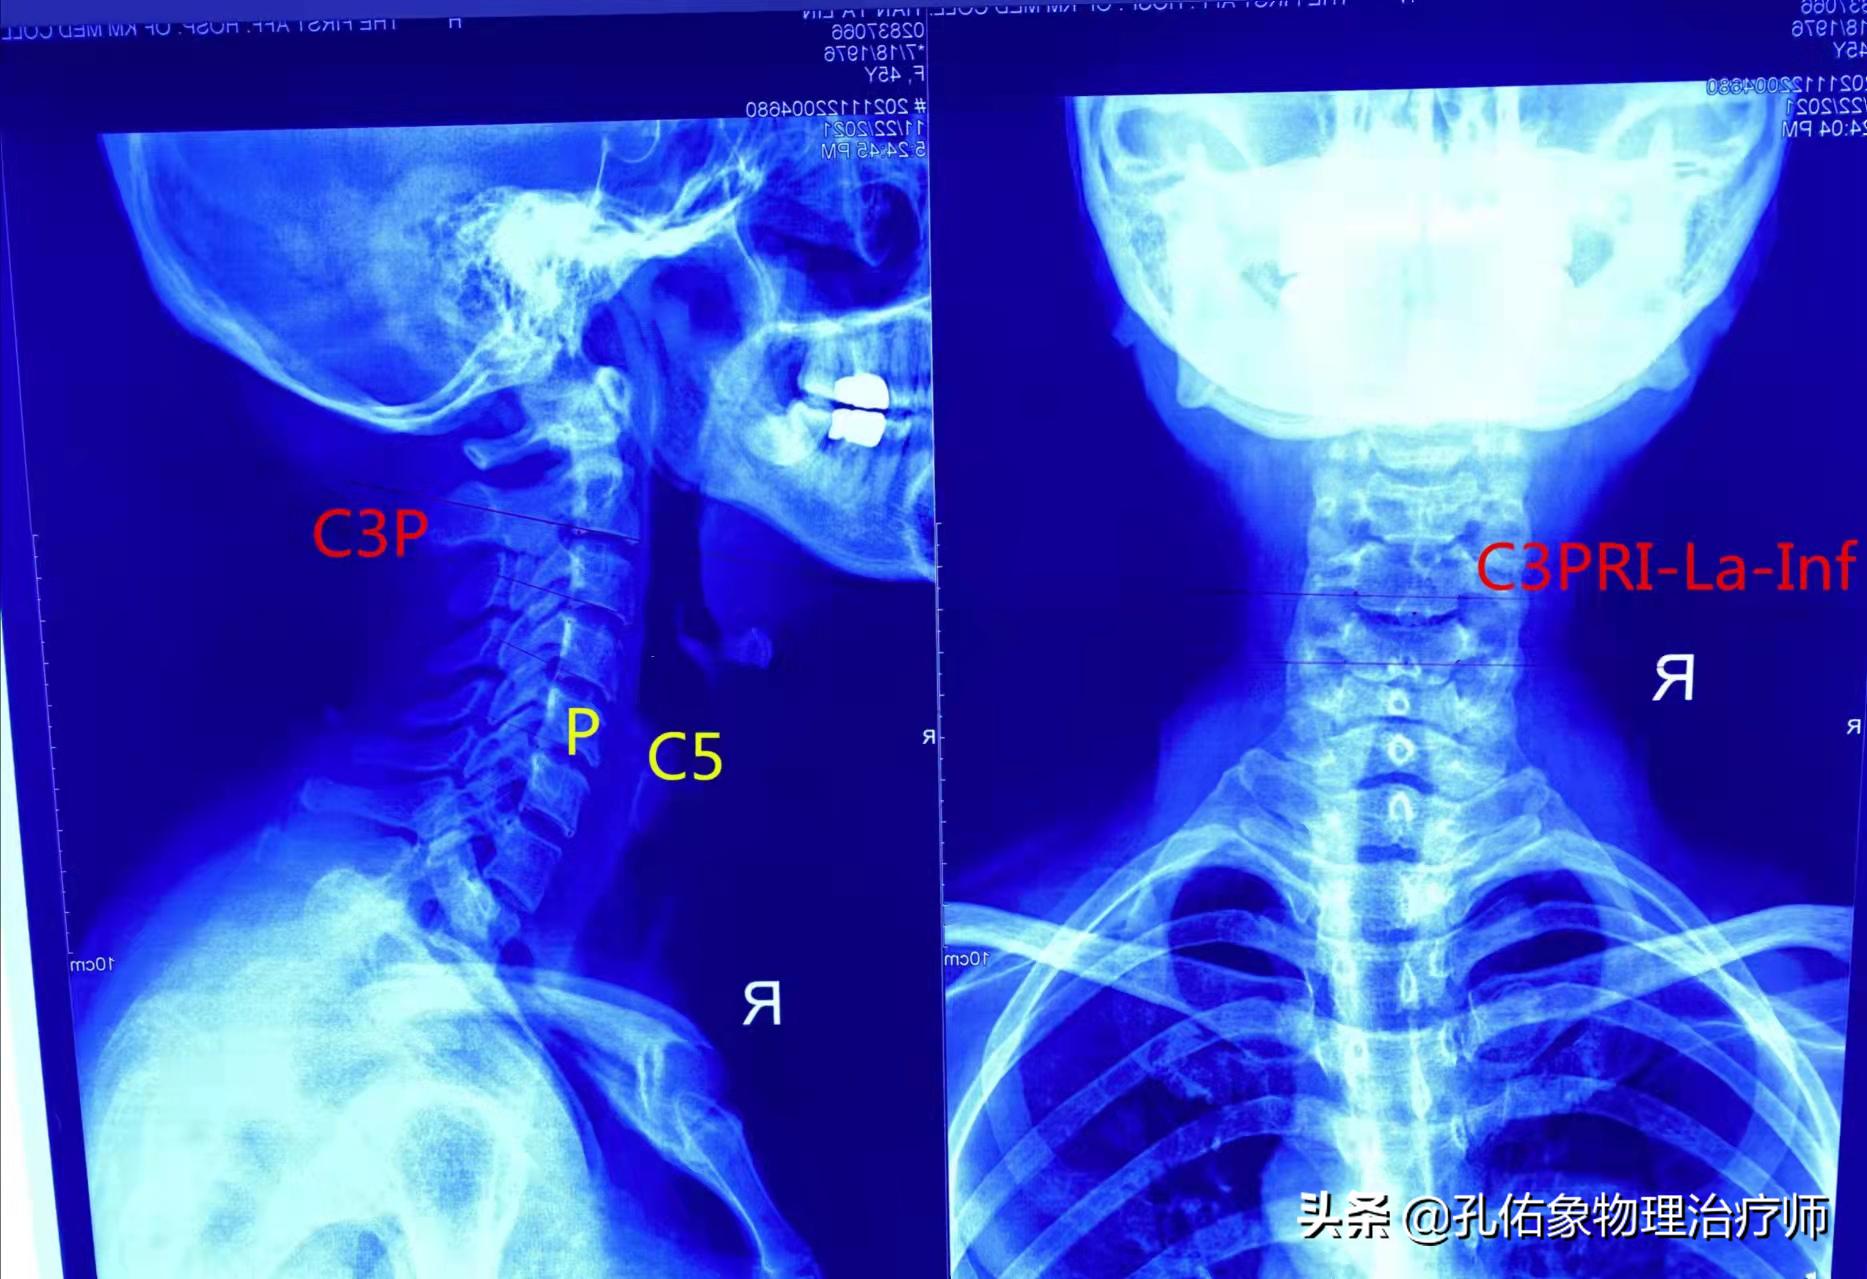

检查有两种途径:一种是徒手评估检查,必须是内行才可做出判断;另一种是拍片,并不是各位拿着的颈部核磁,需要颈部的X片才能分析是哪节段错位。

2-7节颈椎的片子

第一、二颈椎的片子

分析片子的过程非常重要,并不是像影像科大夫给您的报告那样,颈椎生理曲度退变、角弓反张、骨质增生等,这些都是对治疗毫无意义的。只 有专业的分析、画片之后找出问题所在,治疗才有针对性。#健康2022#